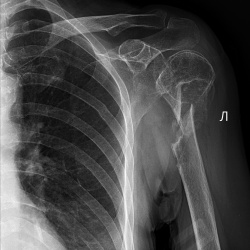

Пришел травматолог на дежурстве, привез на КТ по cito бабушку 63 лет; в анамнезе инсульт несколько месяцев как, плегия.

Также в анамнезе какая-то травма плеча и очень активные родственники,...